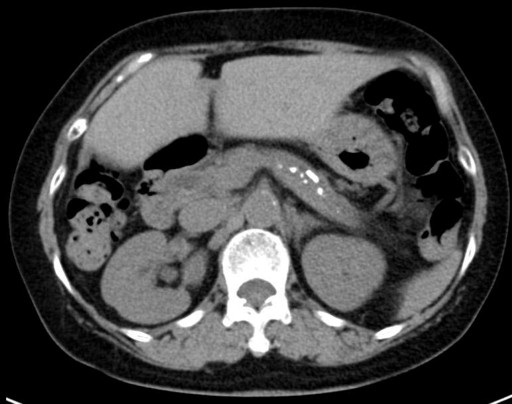

Seven years after clinical onset, abdominal CT revealed multiple pancreatic stones in an atrophic pancreas (Figure 2). ERCP (Figure 3) and magnetic resonance cholangiopancreatography (MRCP) (Figure 3) revealed stenosis of the main pancreatic duct in the head of the pancreas and upstream dilatation. MRCP (Figure 4) and ERC (Figure 5) revealed a longer stretch of stenosis in the hilar hepatic region. We tried steroid therapy in an attempt to ameliorate the stenosis of both the bile duct and the pancreatic duct, and prevent further progression. The initial dose of prednisolone was 30 mg, and this was gradually reduced. Two weeks, 7 weeks, and 11 weeks after the start of prednisolone administration, MRCP revealed no improvement of either the bile duct stenosis or the diffuse irregularity of the main pancreatic duct. The atrophic pancreas showed no change in size. The serum IgG and IgG4 levels decreased from 1,463 to 756 mg/dL (reference range: 870-1,700 mg/dL), and from 127 to 32.9 mg/dL, respectively. The steroid therapy was therefore stopped because of its ineffectiveness and the worsening of diabetes mellitus.

Figure 2. Abdominal CT showing multiple pancreatic stones in an atrophic pancreas. |